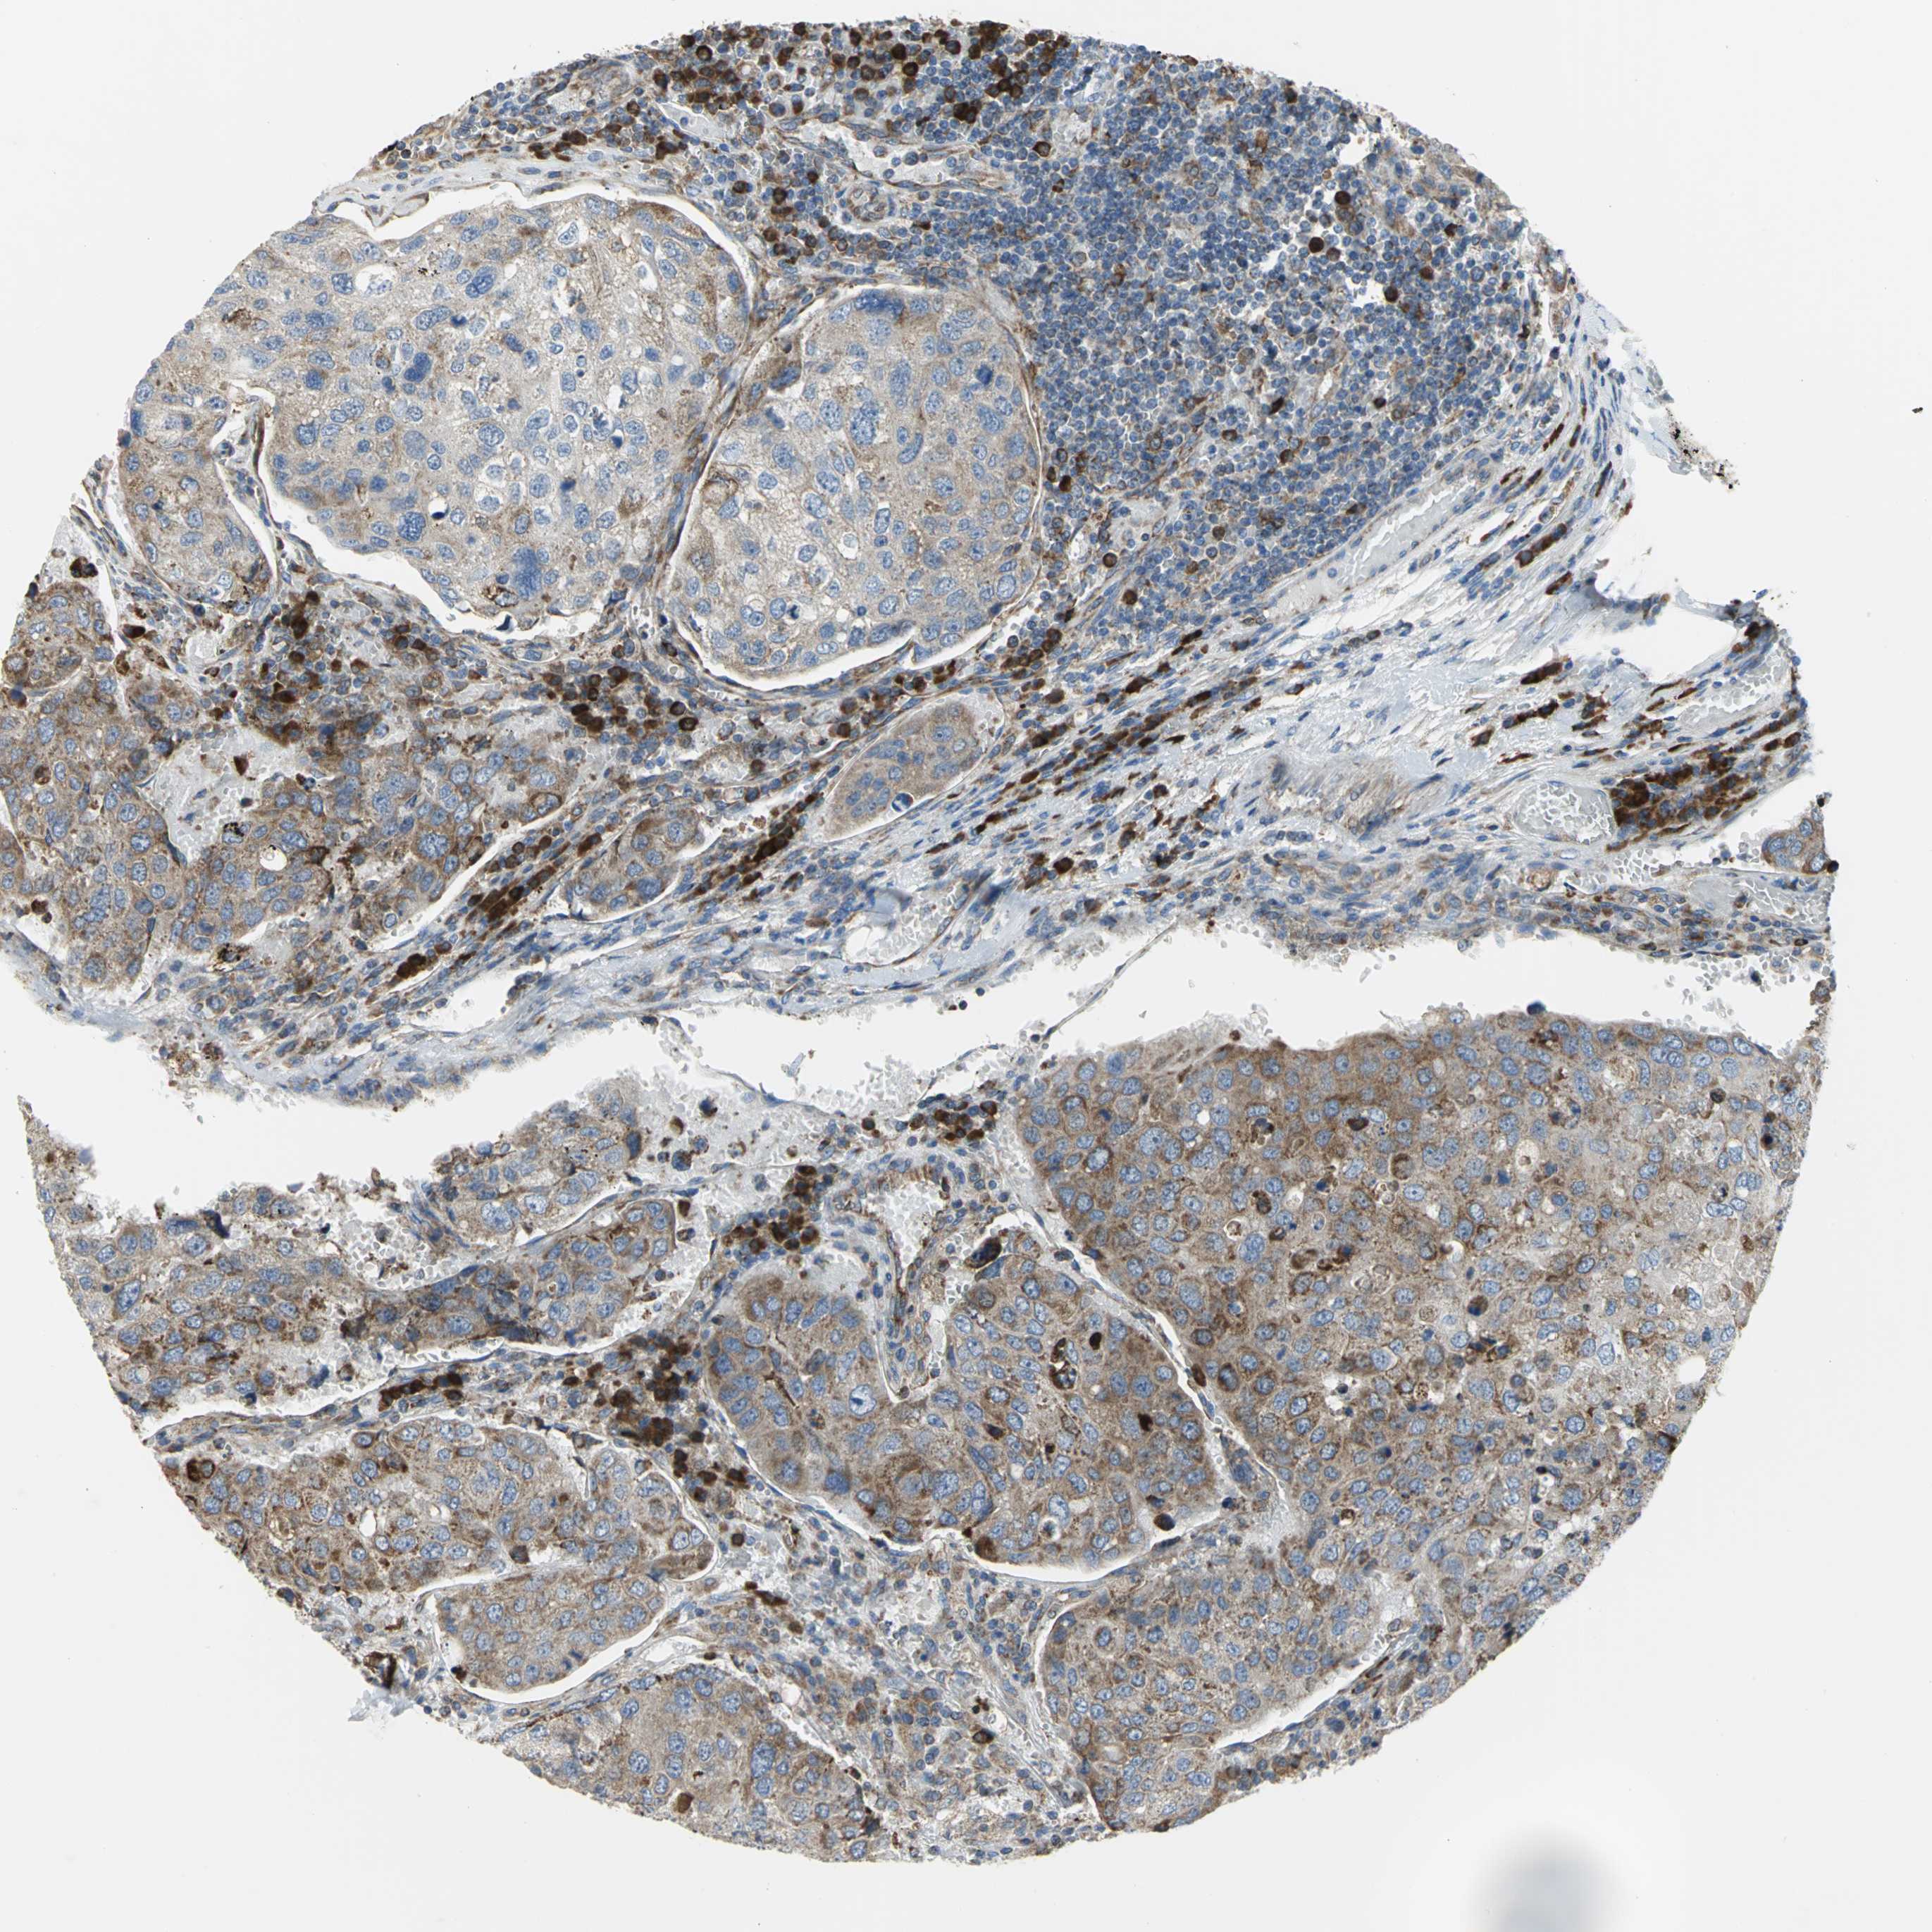

UROTHELIAL CANCER - Protein expressioni

A mouse-over function shows sample information and annotation data. Click on an image to view it in a full screen mode. Samples can be filtered based on level of antibody staining by selecting one or several of the following categories: high, medium, low and not detected. The assay and annotation is described here.

Note that samples used for immunohistochemistry by the Human Protein Atlas do not correspond to samples in the TCGA dataset.

Antibody stainingi

Antibody staining in the annotated cell types in the current human tissue is reported as not detected, low, medium, or high, based on conventional immunohistochemistry profiling in selected tissues. This score is based on the combination of the staining intensity and fraction of stained cells.

Each image is clickable and will lead to virtual microscopy that enables deeper exploration of all samples and also displays staining intensity scores, fraction scores and subcellular localization as well as patient and tissue information for each sample.

Antibody HPA005445

Staining

High

Medium

Low

Not detected

Intensity

Strong

Moderate

Weak

Negative

Quantity

>75%

75%-25%

<25%

None

Location

Nuclear

Cytoplasmic/membranous

Cytoplasmic/membranous,nuclear

Urothelial carcinoma, High grade

Urothelial carcinoma, Low grade